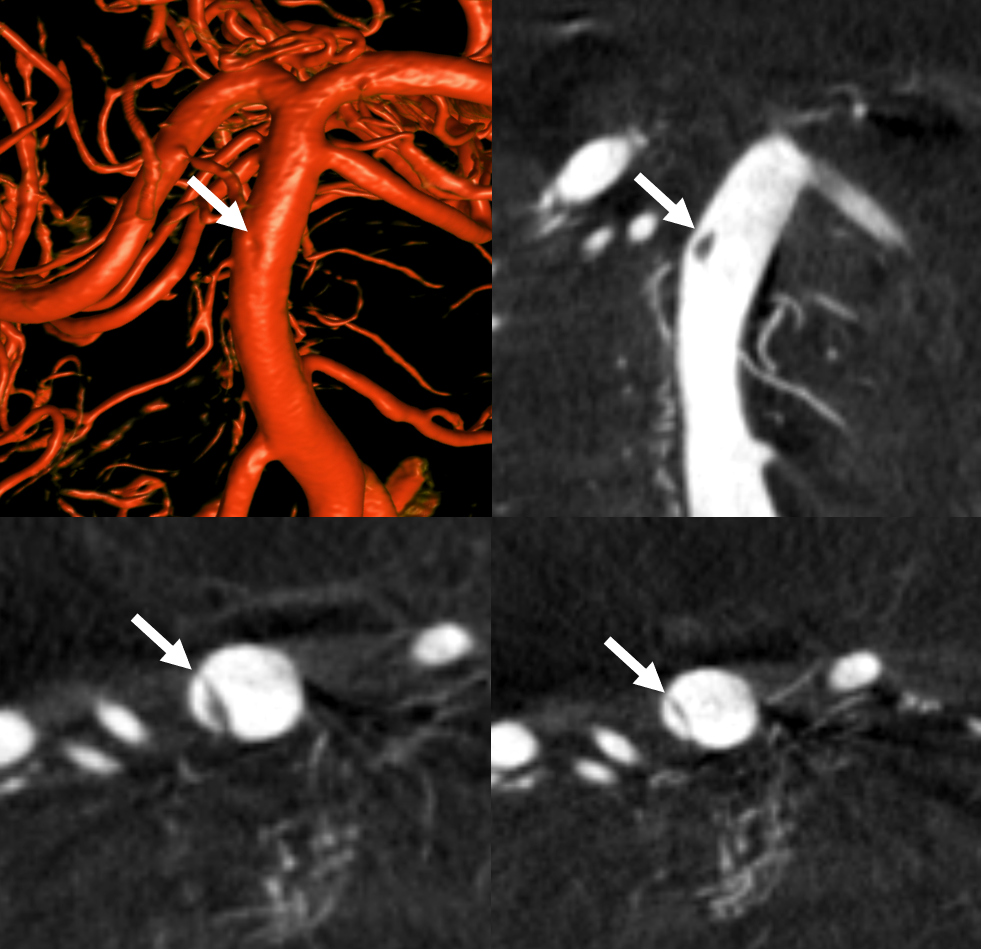

Pre and post thrombectomy images — note unusual filling defect (white arrow) in the upper right basilar before and after thrombectomy (dashed black arrow = clot). This is not iatrogenic — was present from getgo.

DYNA — Siemens Q10 second micro FOV 22 cm dual volume 100% contrast injection — 3 for 36 2 second delay, with secondary reconstruction. Dissection flap – arrows, best seen on MIP images.